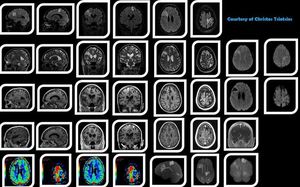

High-resolution, multiparametric (anatomical, functional quantitative) MR Imaging of brain metastases, based on volumetric acquisitions (3D T2, 3D T2 FLAIR, 3D T1 pre post contrast, 3D SWI), DWI, PWI and advanced image post-processing in order to aid the diagnosis.